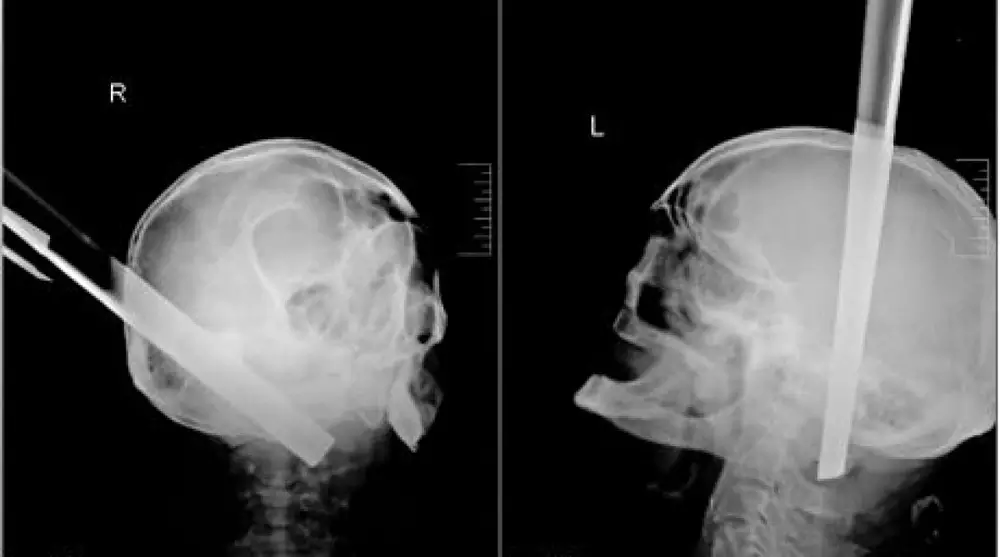

Мужчину с ножкой от табурета в голове спасли в России Фото ©kraszdrav.ru

В России врачи спасли жизнь мужчине, который прибыл в больницу с металлической ножкой от табурета в голове, сообщает NEWSru.com Как поясняет издание, ножка пробила пациенту полость черепа в затылочной части и прошла на 11 сантиметров вглубь его основания сквозь вещество головного мозга. В экстренном порядке мужчине была проведена операция. По словам медиков, процедура прошла без осложнений, даже несмотря на удаление столь массивного предмета - у больного даже не возникло ожидаемого кровотечения. После операции, которая длилась около трех часов, мужчина две недели провел в нейрореанимации в тяжелом состоянии. Затем его состояние стабилизировалось. В настоящее время угрозы для его жизни нет. Он находится в сознании, может самостоятельно принимать пищу. "Он в сознании, имя и фамилию называет, но пока не помнит подробности, при которых получил травму", - сказал нейрохирург Павел Руденко.